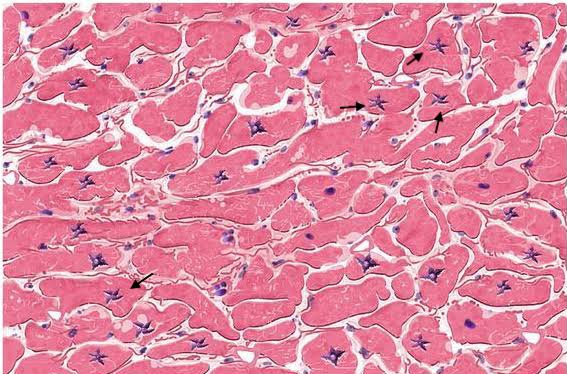

Most likely diagnosis for this histology slide? #neetpg2026 #MedTwitter Chaudhary Shafiullah Dr. Shiv_Kumar C.Alberto Ortega Dr. Akhil 🇮🇳 Dr. Medica🩺 Antonio Arroyo, MD. Medico Cirujano.